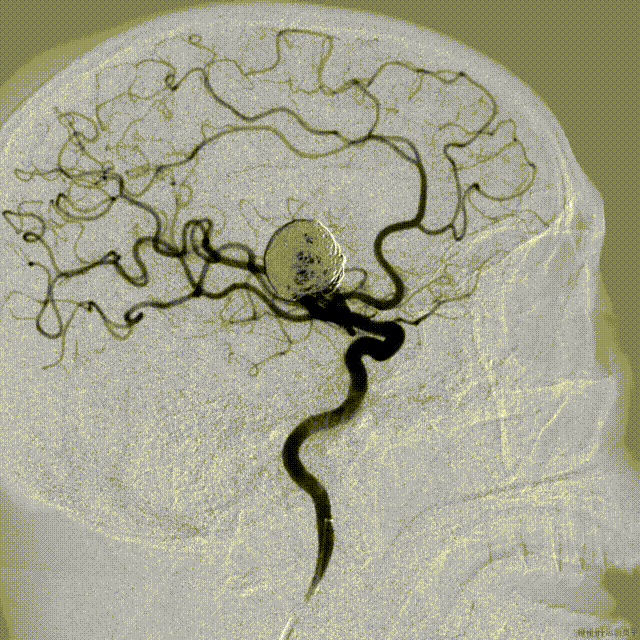

术前影像

术前正位DSA

术前侧位DSA

术前CT

初步诊断:右侧大脑中动脉M1动脉瘤

侧别、位置:右侧

动脉瘤的形态:囊性

动脉瘤大小:长15.0mm、宽16.6mm、高15.1mm

动脉瘤颈宽度:12.0mm

载瘤动脉直径:远端3.8mm,近端4.6mm

治疗方案:Lattice血流导向密网支架置入术+弹簧圈辅助栓塞